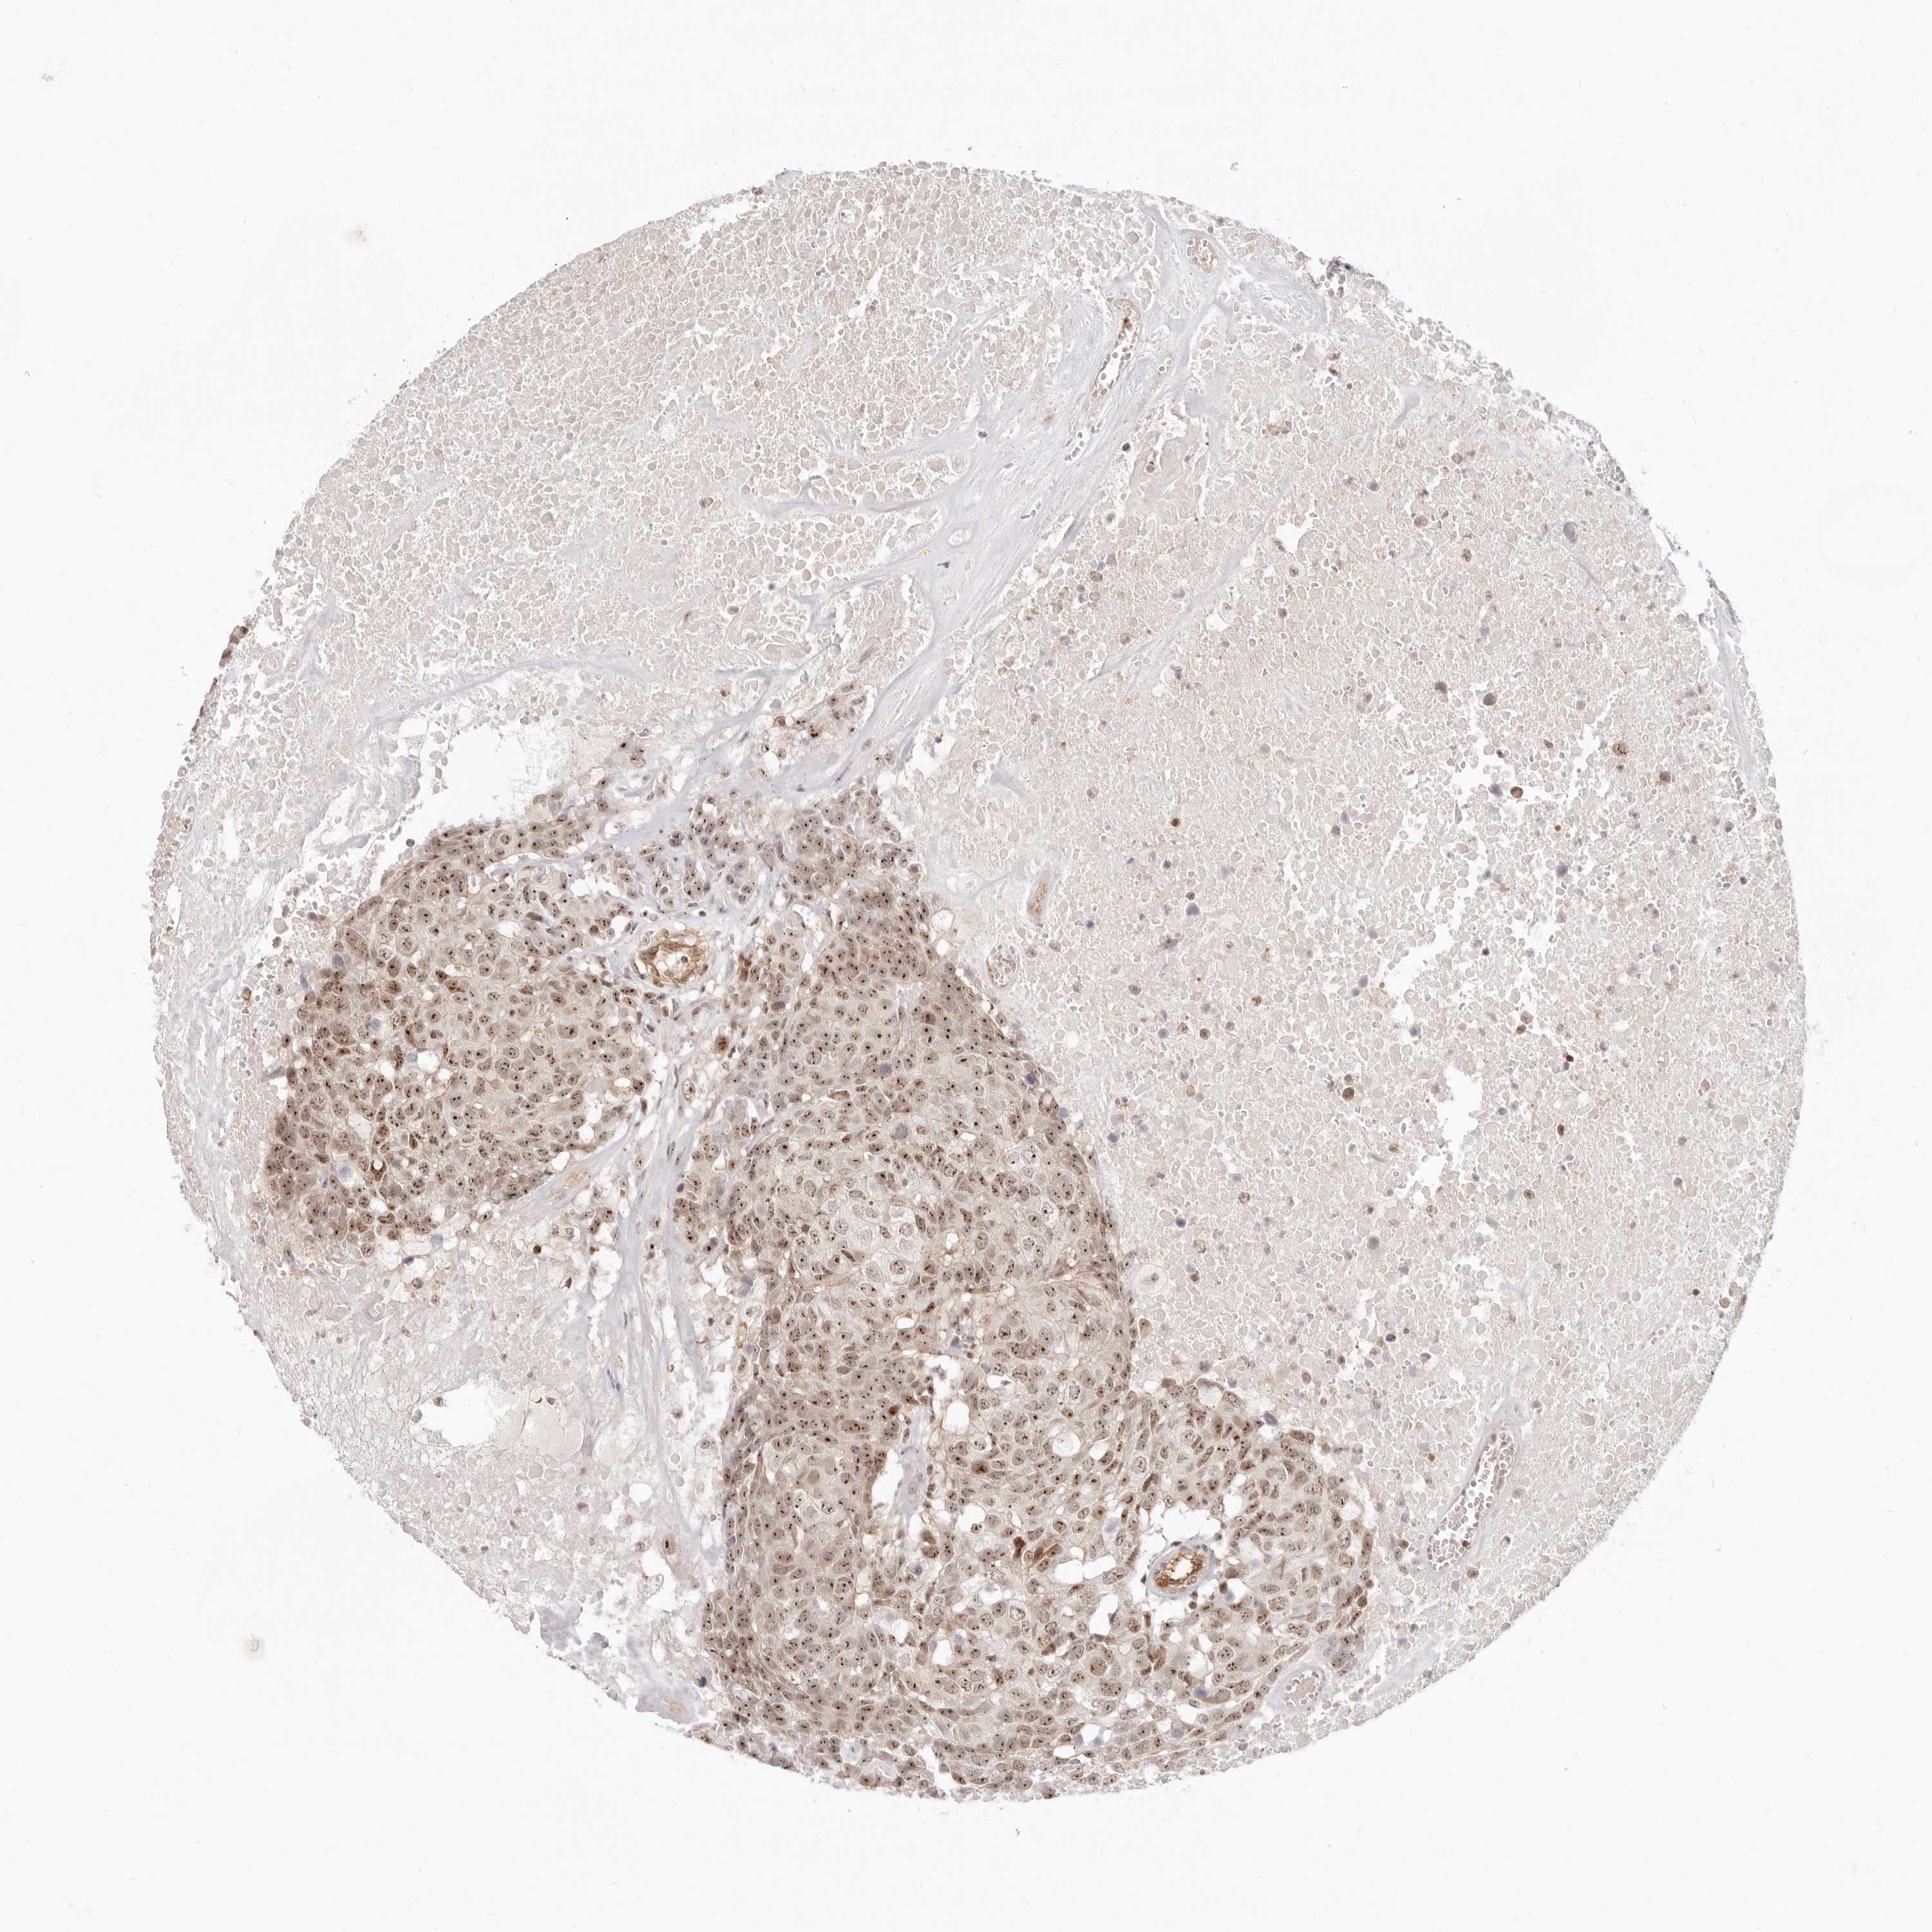

HEAD AND NECK CANCER - Protein expressioni

A mouse-over function shows sample information and annotation data. Click on an image to view it in a full screen mode. Samples can be filtered based on level of antibody staining by selecting one or several of the following categories: high, medium, low and not detected. The assay and annotation is described here.

Antibody stainingi

Antibody staining in the annotated cell types in the current human tissue is reported as not detected, low, medium, or high, based on conventional immunohistochemistry profiling in selected tissues. This score is based on the combination of the staining intensity and fraction of stained cells.

Each image is clickable and will lead to virtual microscopy that enables deeper exploration of all samples and also displays staining intensity scores, fraction scores and subcellular localization as well as patient and tissue information for each sample.

Antibody HPA028814

Squamous cell carcinoma, NOS

Squamous cell carcinoma, metastatic, NOS

Adenocarcinoma, NOS

Neoplasm, malignant, NOS